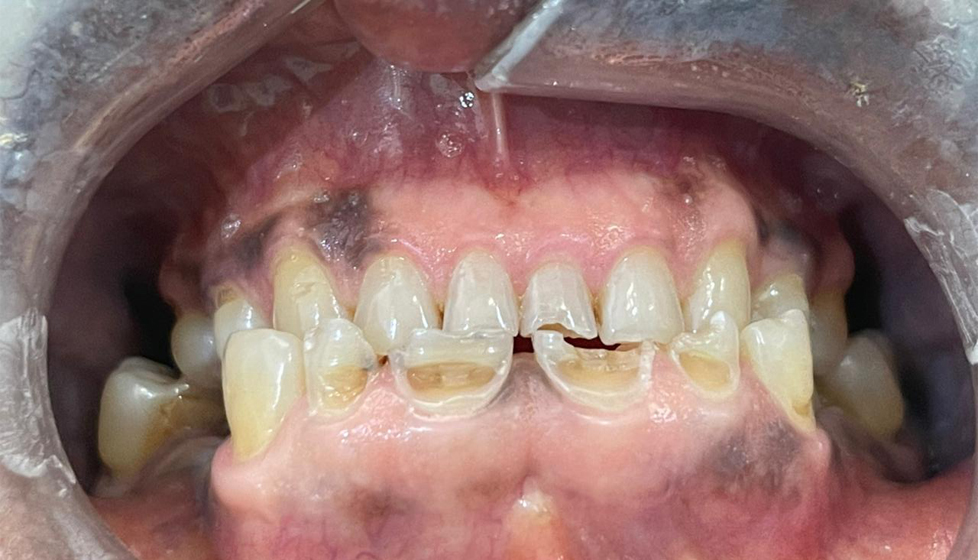

Les soins dentaires en tourisme médical offrent aux patients internationaux l’opportunité de bénéficier de traitements de haute qualité

Des améliorations visibles et mesurables

Transformations visibles : avant et après